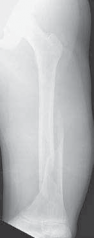

Chapter 1 Intramedullary Fixation of Forearm Shaft Fractures Charles T. Mehlman DEFINITION Forearm shaft fr…